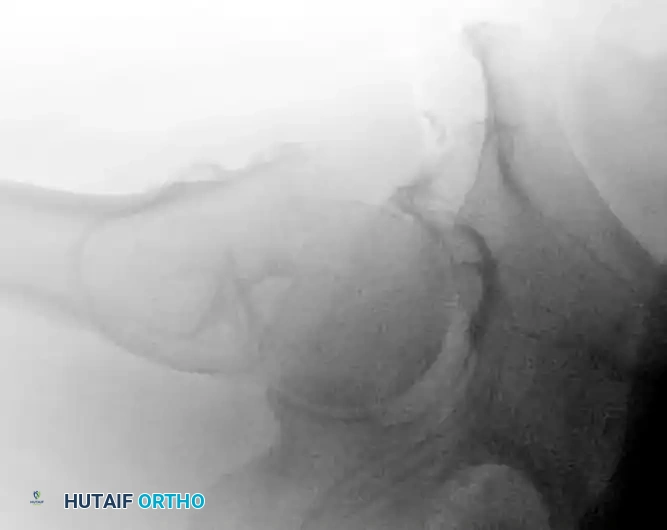

CLOSED REDUCTION MANEUVERS

Surgical Warning: Never proceed with the surgical incision until an acceptable closed reduction is confirmed on both AP and lateral fluoroscopic views. A poorly reduced fracture cannot be salvaged by a perfectly placed implant.

- Standard Reduction: Reduction of the affected extremity is typically achieved through longitudinal traction followed by internal rotation. The internal rotation corrects the external rotation deformity caused by the short external rotators and gravity, bringing the femoral neck parallel to the floor.

- Correcting Sagittal Deformity: The most common sagittal plane deformity is a posterior sag of the fracture site. This may require correction via an anteriorly applied force (e.g., a crutch or a specialized reduction tool placed under the posterior thigh) to lift the distal fragment before finalizing the reduction with traction and internal rotation.

- Fluoroscopic Scrutiny: Carefully scrutinize the images to rule out varus deformity, posterior sag, and excessive internal rotation. A slight valgus reduction is biomechanically superior to any degree of varus.